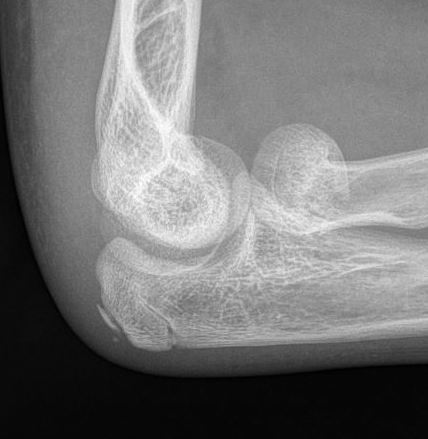

Retrograde flexible nail

Technique

Entry point through radial styloid

- closed reduction +/- percutaneous K wire reduction

- engage tip into radial neck

- Metaizeau technique - rotate nail to reduce radial fracture